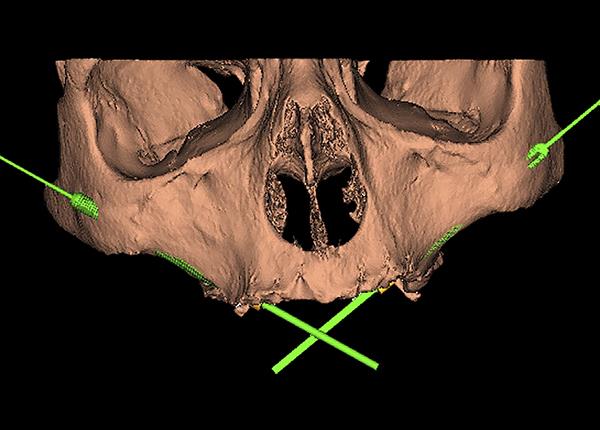

- Initial evaluation and surgical planning – when you reach out to our Dental clinic, the dentist or the surgeon will conduct a thorough examination and take scans like 3-D imaging cone beam CT scans, Digital intra-oral scans to assess your bone structure and plan the implant placement.

- Surgical placement – the surgery is performed under general anaesthesia or under local anesthesia. The type of Anesthesia depends on the patient’s and surgeon’s comfort ability. The surgeon makes small incision in the gum tissue and carefully dissect to reach the bone and places the zygomatic implants into the cheekbone. It is placed in a planned angulation and depth. In complicated cases a surgical guide is utilized to place the Implants.In many cases a temporary processes can be loaded immediately allowing you to leave the clinic with a full functional smile.

- Sinusitis – when the implant penetrate the sinus membrane inflammation of the sinus cavity can occur.

- Nerve damage – proximity of facial nerve and infraorbital nerve may lead in temporary or permanent numbness during the placement and the recovery period.

Due to improved medical facilities and thorough preoperative planning using 3-D scans with skilled surgical techniques these risks can be minimised. Choose your clinician or Surgeon wisely.